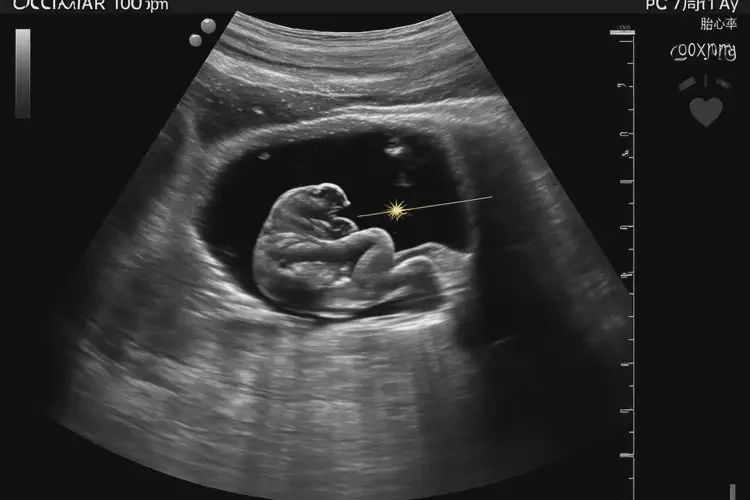

孕7周1天胎心100寶寶還能要嗎

胎心100次/分鐘在孕7周1天屬于正常范圍,寶寶可以要。

在孕7周1天時,胎兒的胎心率在100次/分鐘是正常的。胎心率是指胎兒心臟每分鐘跳動的次數(shù),通常在孕早期(6-8周),胎心率的范圍在90-110次/分鐘之間。胎心100次/分鐘并不意味著寶寶有問題,可以繼續(xù)妊娠。

孕7周1天胎心100寶寶還能要嗎(圖1)